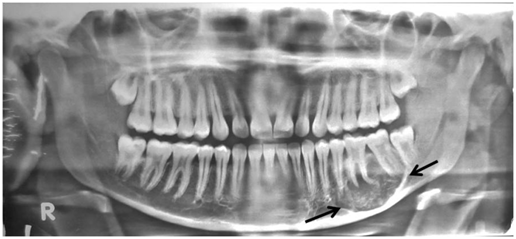

An 18year old female patient reported to the department of Oral Pathology, Dr. R Ahmed Dental College & Hospital, Kolkata with a complaint of swelling since 2years on the lower left jaw (Figure 1). The swelling was slow growing and painless. It was visible on the left side of the mandible and extended from left lower canine to left lower 2nd molar tooth (Figure 2). It was found as bony hard in consistency and non tender on palpation. Intra-oral examination revealed a dome shaped swelling measured approximately 4cmx3cm present on buccal vestibule of left mandible without any ulceration on overlying mucosa. The teeth involved were mobile and tender to pressure and percussion. Panoromic X ray revealed a distinct radio-lucency of approximately 5cmx3cm in size while scattered radio opacity was observed throughout the lesion (Figure 3). From this, the lesion could be provisionally diagnosed as fibro-osseous lesion/ameloblastoma. A biopsy was performed with local anesthesia and microscopic examination revealed fibro cellular stroma with multiple round oval hematoxyphilic calcified matrix similar to cementum/osteoid like material. There were no atypia or mitotic figures (Figure 4). These observations were consistent with cement ossifying fibroma. The management consisted of conservative surgical excision by curettage enucleation under local anesthesia raising mucoperiosteal flap. Post operative follow up was advised and after 6 month follow up the patient not reported any discomfort and panoromic X ray confirmed good bone regeneration in the operative zone.

Figure 3 Panoromic X ray of Jaws showing well-defined radiolucent lesion with patchy mineralization (arrows)